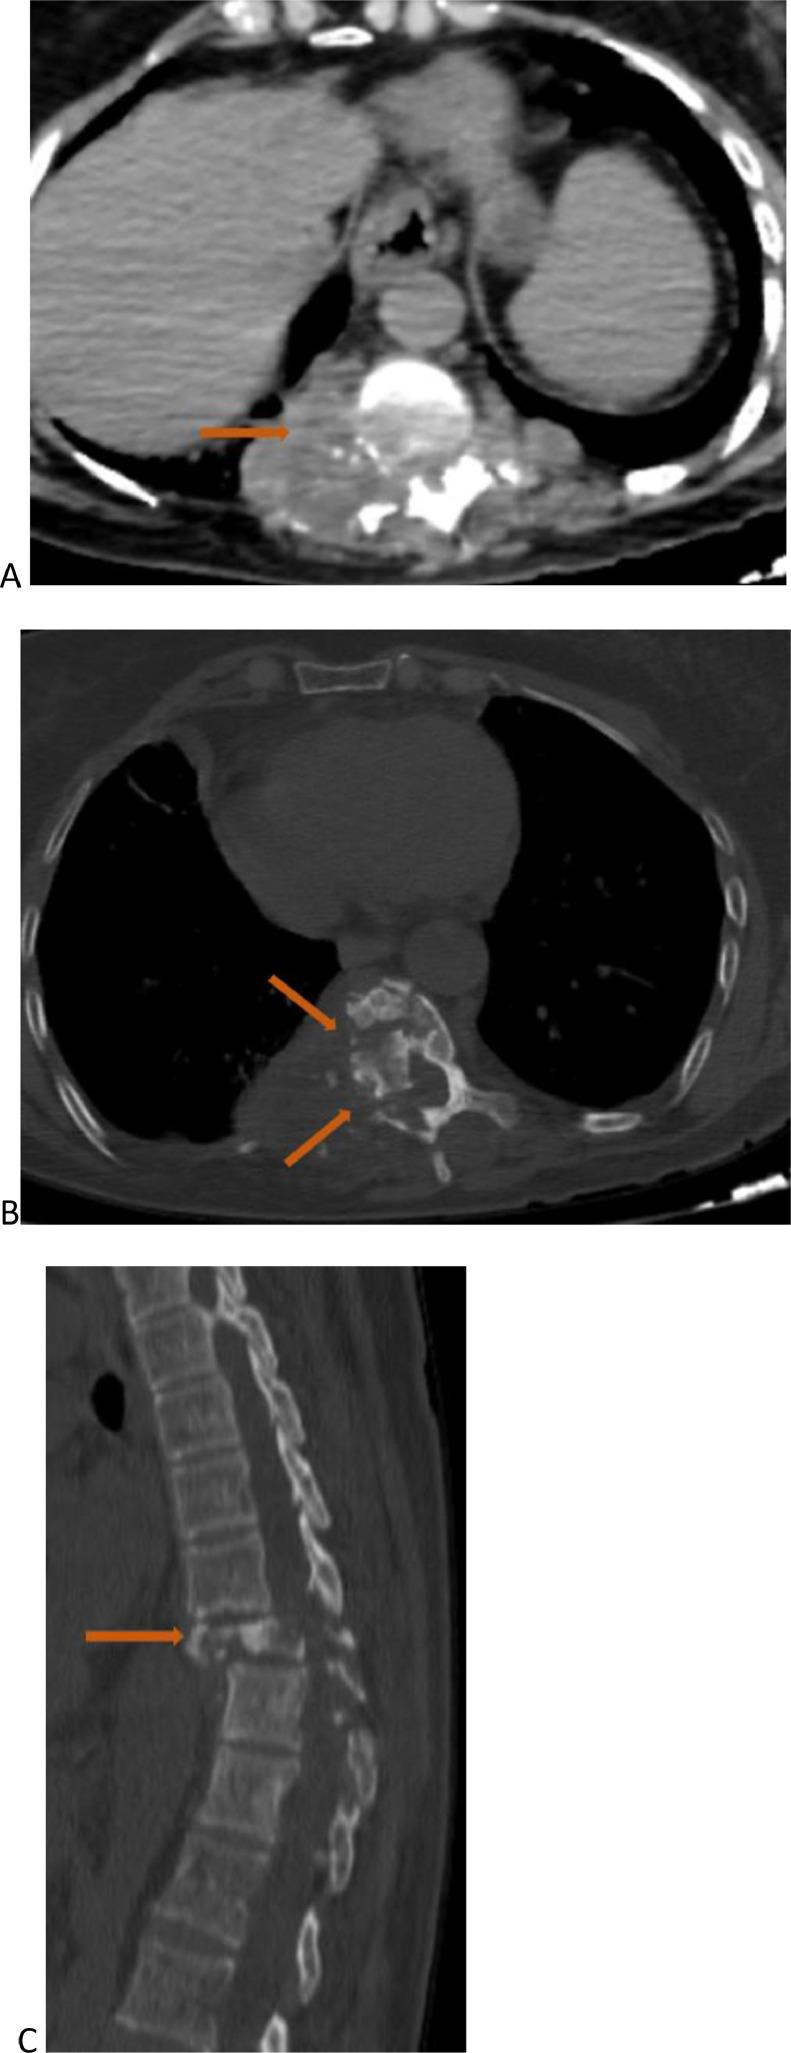

原发性脊椎-髓内及硬膜外包虫病导致髓质受压的罕见病因影像学表现:影像学的作用

Iconographies of rare causes of medullary compression due to primary vertebro-medullary and epidural hydatidosis: Contribution of imaging.

Vertebro-medullary and epidural hydatidosis are a very rare entity, representing 2% of all locations, and is even rarer when it involves a solitary location. It is often asymptomatic. The diagnosis is usually made during complications, particularly medullary compression or extension to the costal cage, which represents a therapeutic emergency. Surgical treatment must be radical to prevent recurrences. We report 2 cases: the first case was a 61-year-old female involved costo-vertebral hydatidosis, and the second was an 18-year-old man with primary sacral epidural location. The objective of our report is to add these 2 atypical locations of hydatid cysts to the existing literature and to present their radiological images to aid radiologists in diagnosis.

摘要

脊椎-髓内和硬膜外包虫病是一种非常罕见的疾病,占所有发病部位的2%,当它累及单一部位时更为罕见。它通常无症状。诊断通常在出现并发症时做出,特别是髓内压迫或向胸廓扩展,这是一种治疗急症。手术治疗必须彻底以防止复发。我们报告2例:第一例是一名61岁女性,患有肋-椎包虫病,第二例是一名18岁男性,原发性骶部硬膜外发病。我们报告的目的是将这2个包虫囊肿的非典型发病部位补充到现有文献中,并展示其放射影像以帮助放射科医生进行诊断。